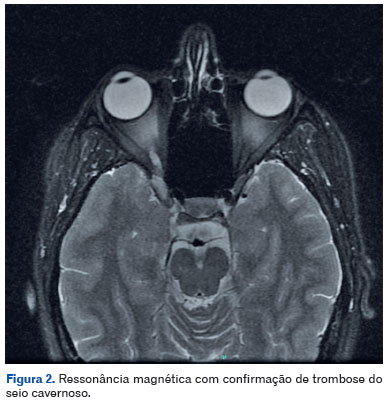

Devido à gravidade do quadro, após avaliação multidisciplinar, foi indicada a interrupção da gestação às 36 semanas, o que permitiu a realização de ressonância magnética com contraste, confirmando o diagnóstico de TSC (Figura 2). Na ausência de causa infecciosa, foi instituída pulsoterapia com metilprednisolona intravenosa (1 g/dia por 3 dias), seguida de prednisona oral 1 mg/kg/dia com desmame gradual. A paciente evoluiu com recuperação completa da acuidade visual (20/20) e resolução da paralisia do terceiro nervo craniano (Figura 3). A ressonância magnética de controle, realizada 10 meses após o evento agudo, demonstrou sinais compatíveis com recanalização parcial da veia oftálmica direita, quando comparada ao estudo anterior.